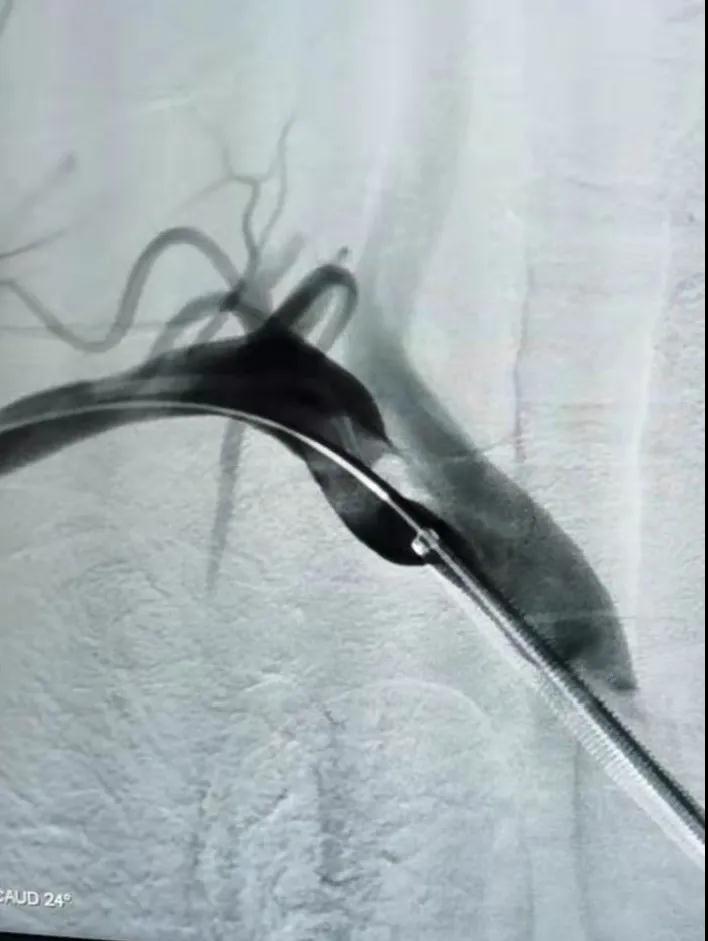

1616144522152973.jpg

開口處閉塞